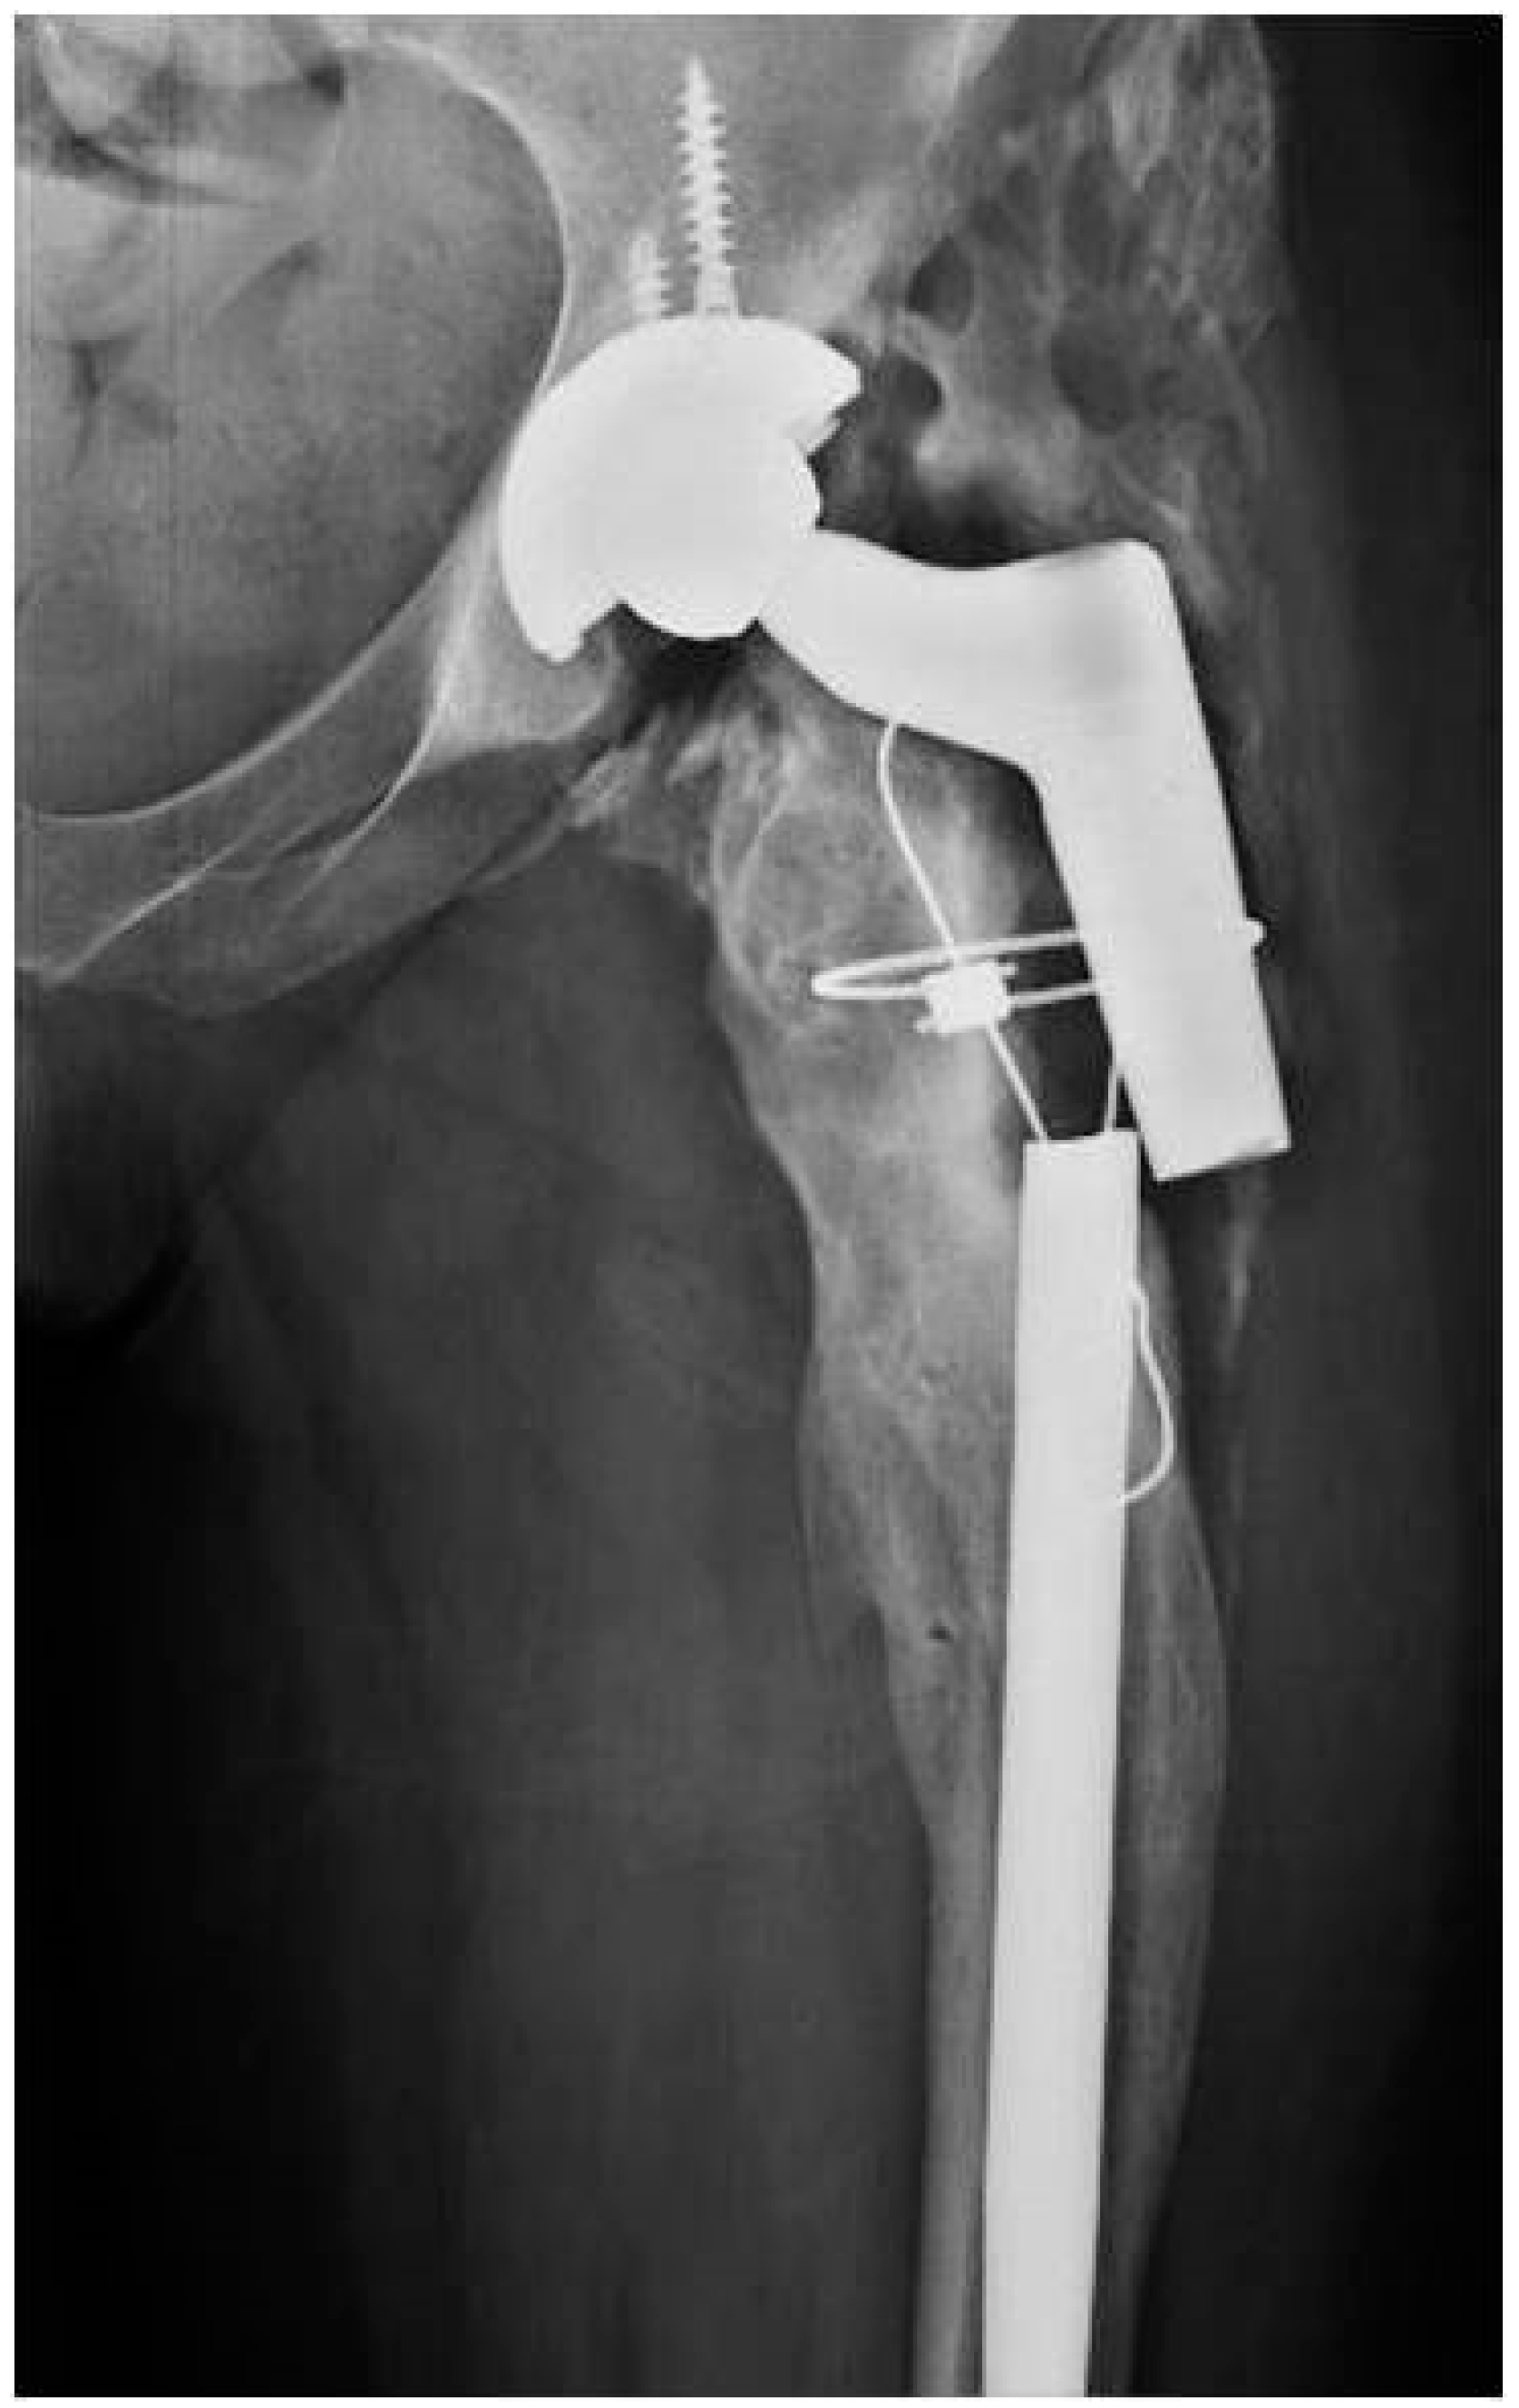

2.1. Case 1